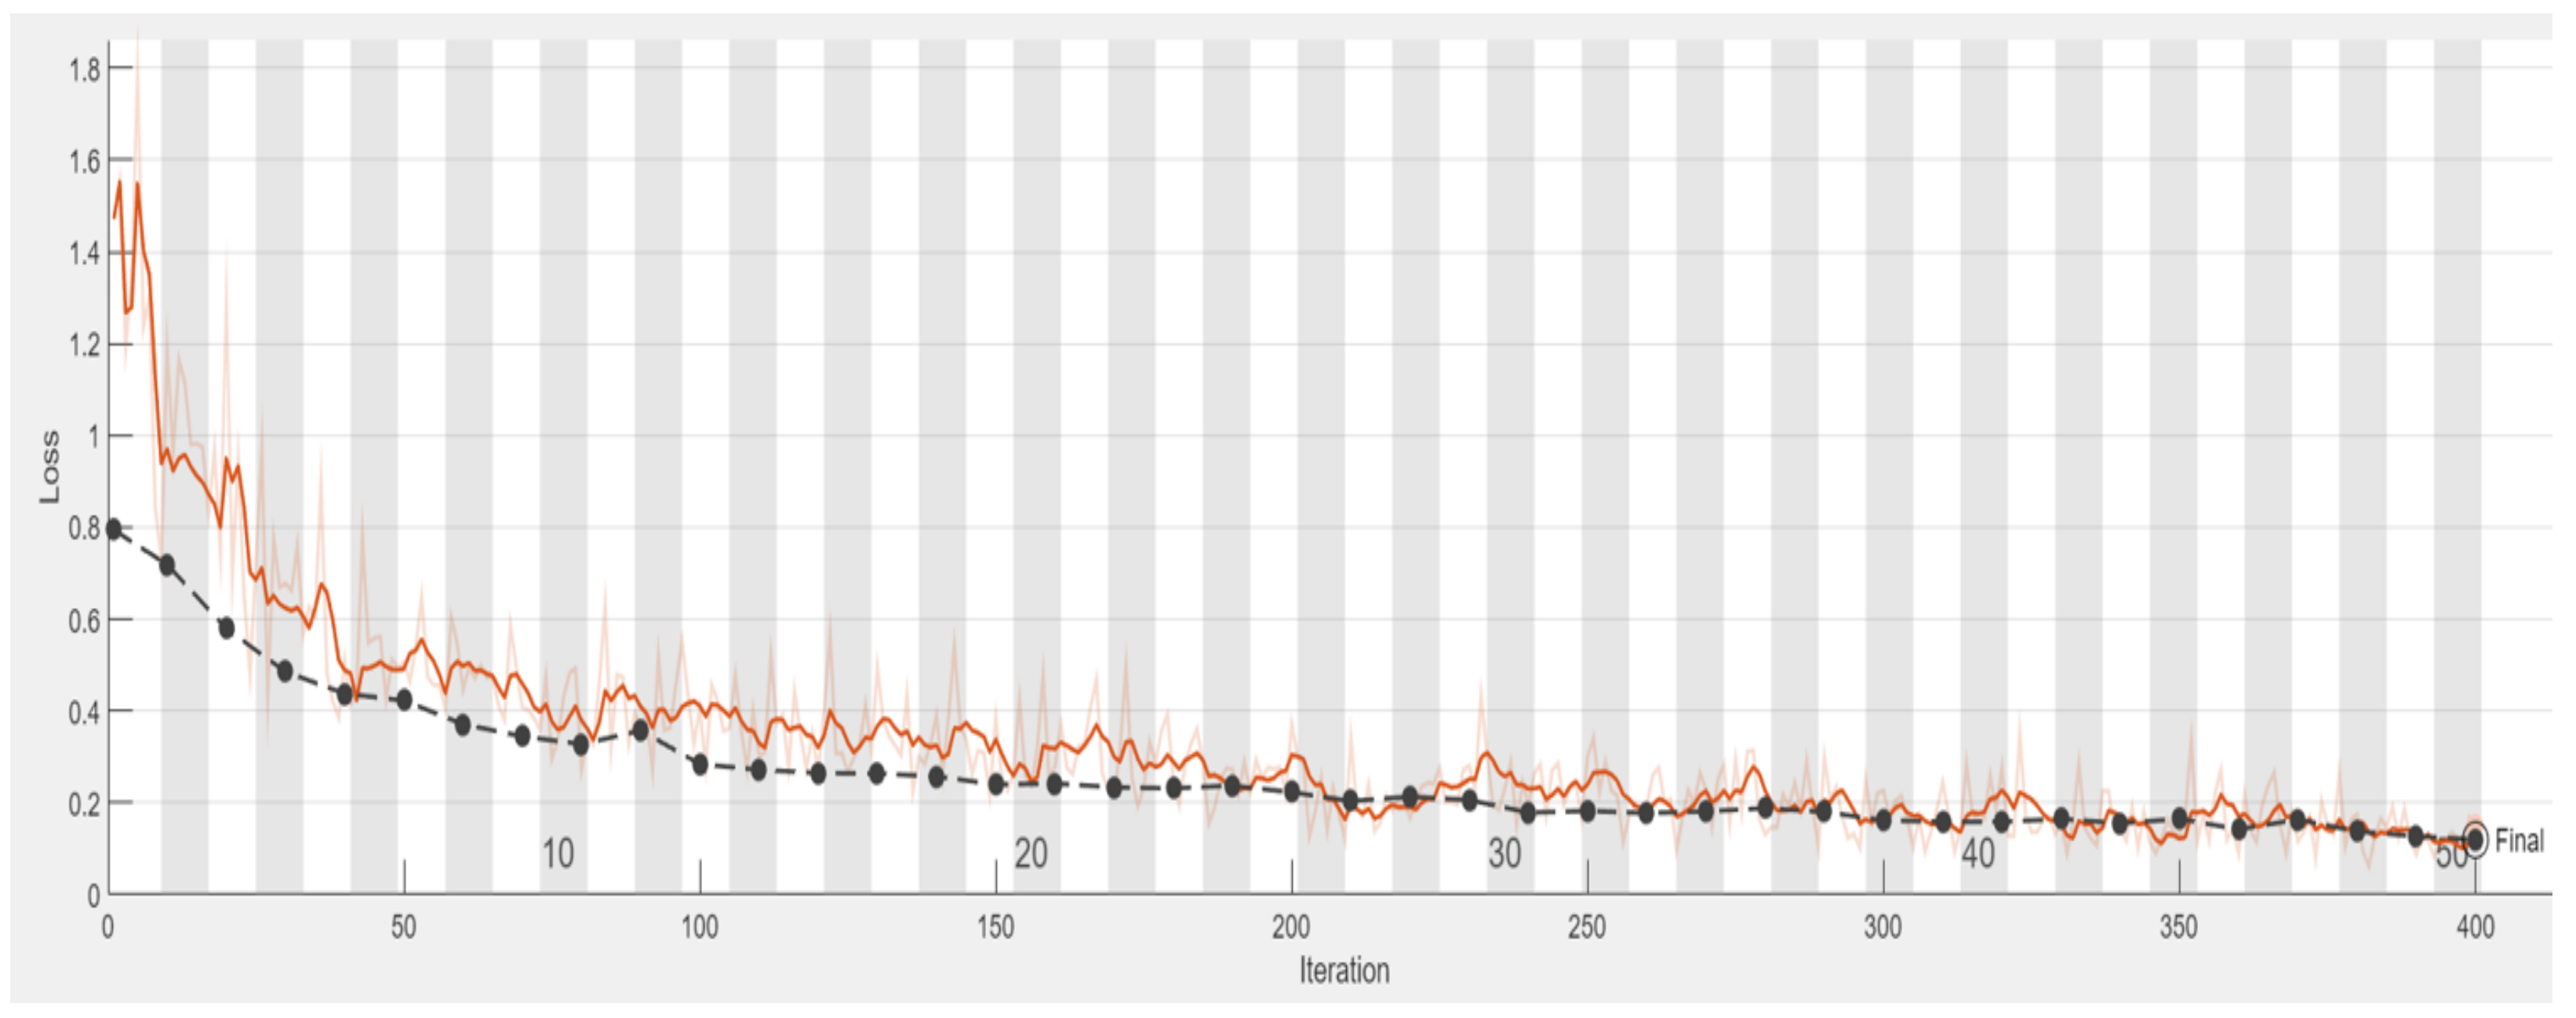

2.3.2. Adjust Hyperparameter

- A.

- Initial Learning Rate

- B.

- Max Epoch

- C.

- Mini Batch Size

| Hyperparameters | Value |

|---|---|

| Initial Learning Rate | 0.0001 |

| Max Epoch | 50 |

| Mini Batch Size | 64 |

| Validation Frequency | 10 |

| Learning Drop Period | 3 |

| Learning Rate Drop Factor | 0.02 |

| Epoch | Iteration | Time Elapsed | Mini-Batch Accuracy | Validation Accuracy | Mini-Batch Loss | Validation Loss |

|---|---|---|---|---|---|---|

| 1 | 1 | 00:00:02 | 48.44% | 53.03% | 1.4716 | 0.7940 |

| 5 | 40 | 00:00:15 | 70.31% | 81.82% | 0.5114 | 0.4379 |

| 10 | 80 | 00:00:27 | 90.62% | 85.61% | 0.2726 | 0.3277 |

| 15 | 120 | 00:00:39 | 90.62% | 88.64% | 0.2668 | 0.2648 |

| 20 | 160 | 00:00:42 | 89.06% | 90.91% | 0.2776 | 0.2422 |

| 25 | 200 | 00:01:03 | 87.50% | 91.67% | 0.3722 | 0.2230 |

| 30 | 240 | 00:01:16 | 90.62% | 93.94% | 0.1955 | 0.1787 |

| 35 | 280 | 00:01:28 | 95.31% | 95.31% | 0.1313 | 0.1883 |

| 40 | 320 | 00:01:41 | 90.62% | 95.45% | 0.2768 | 0.1585 |

| 45 | 360 | 00:01:53 | 96.88% | 95.45% | 0.0896 | 0.1424 |

| 50 | 400 | 00:02:05 | 93.72% | 96.21% | 0.1520 | 0.1201 |